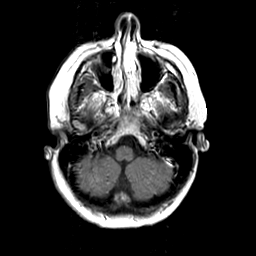

MR Study #3 -- Slice #11

[Home][Help][Clinical][Tour 1][Tour 2][Tour 3] Slice 11